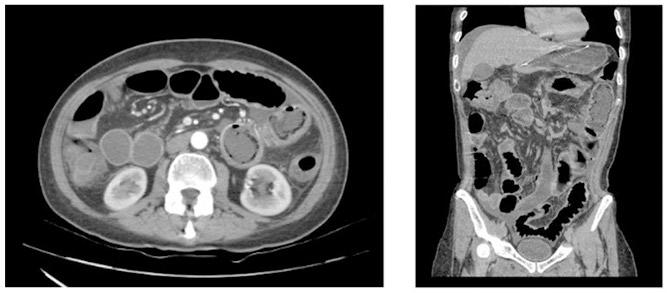

Create a flipbook